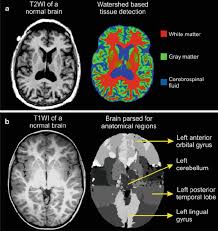

An mri was performed on a healthy subject, with several acquisitions with different weightings:

14+ Anatomy Brain Mri. How to view anatomical labels. The mri sequence used is a 3d gradient echo.

The module interface is meant to mimic a radiology workstation with adjacent image scrolling via arrow keys and. This video shows the appearance of the anatomical structures of the brain on a magnetic resonance imaging.it aims to complement your understanding of. To see images, please update your browser.